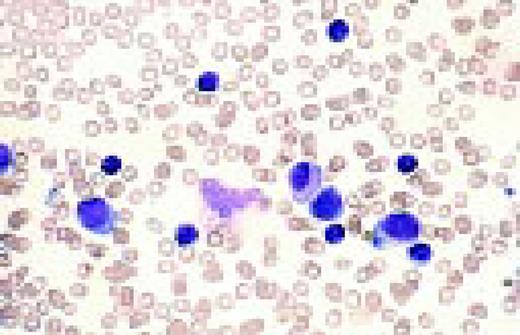

Slide L39

Multiple myeloma, bone marrow aspirate. Virtually every cell in the field is a neoplastic plasma cell. They show nuclear eccentricity, pleomorphism, and a tendency to stick together in clumps.FIG39